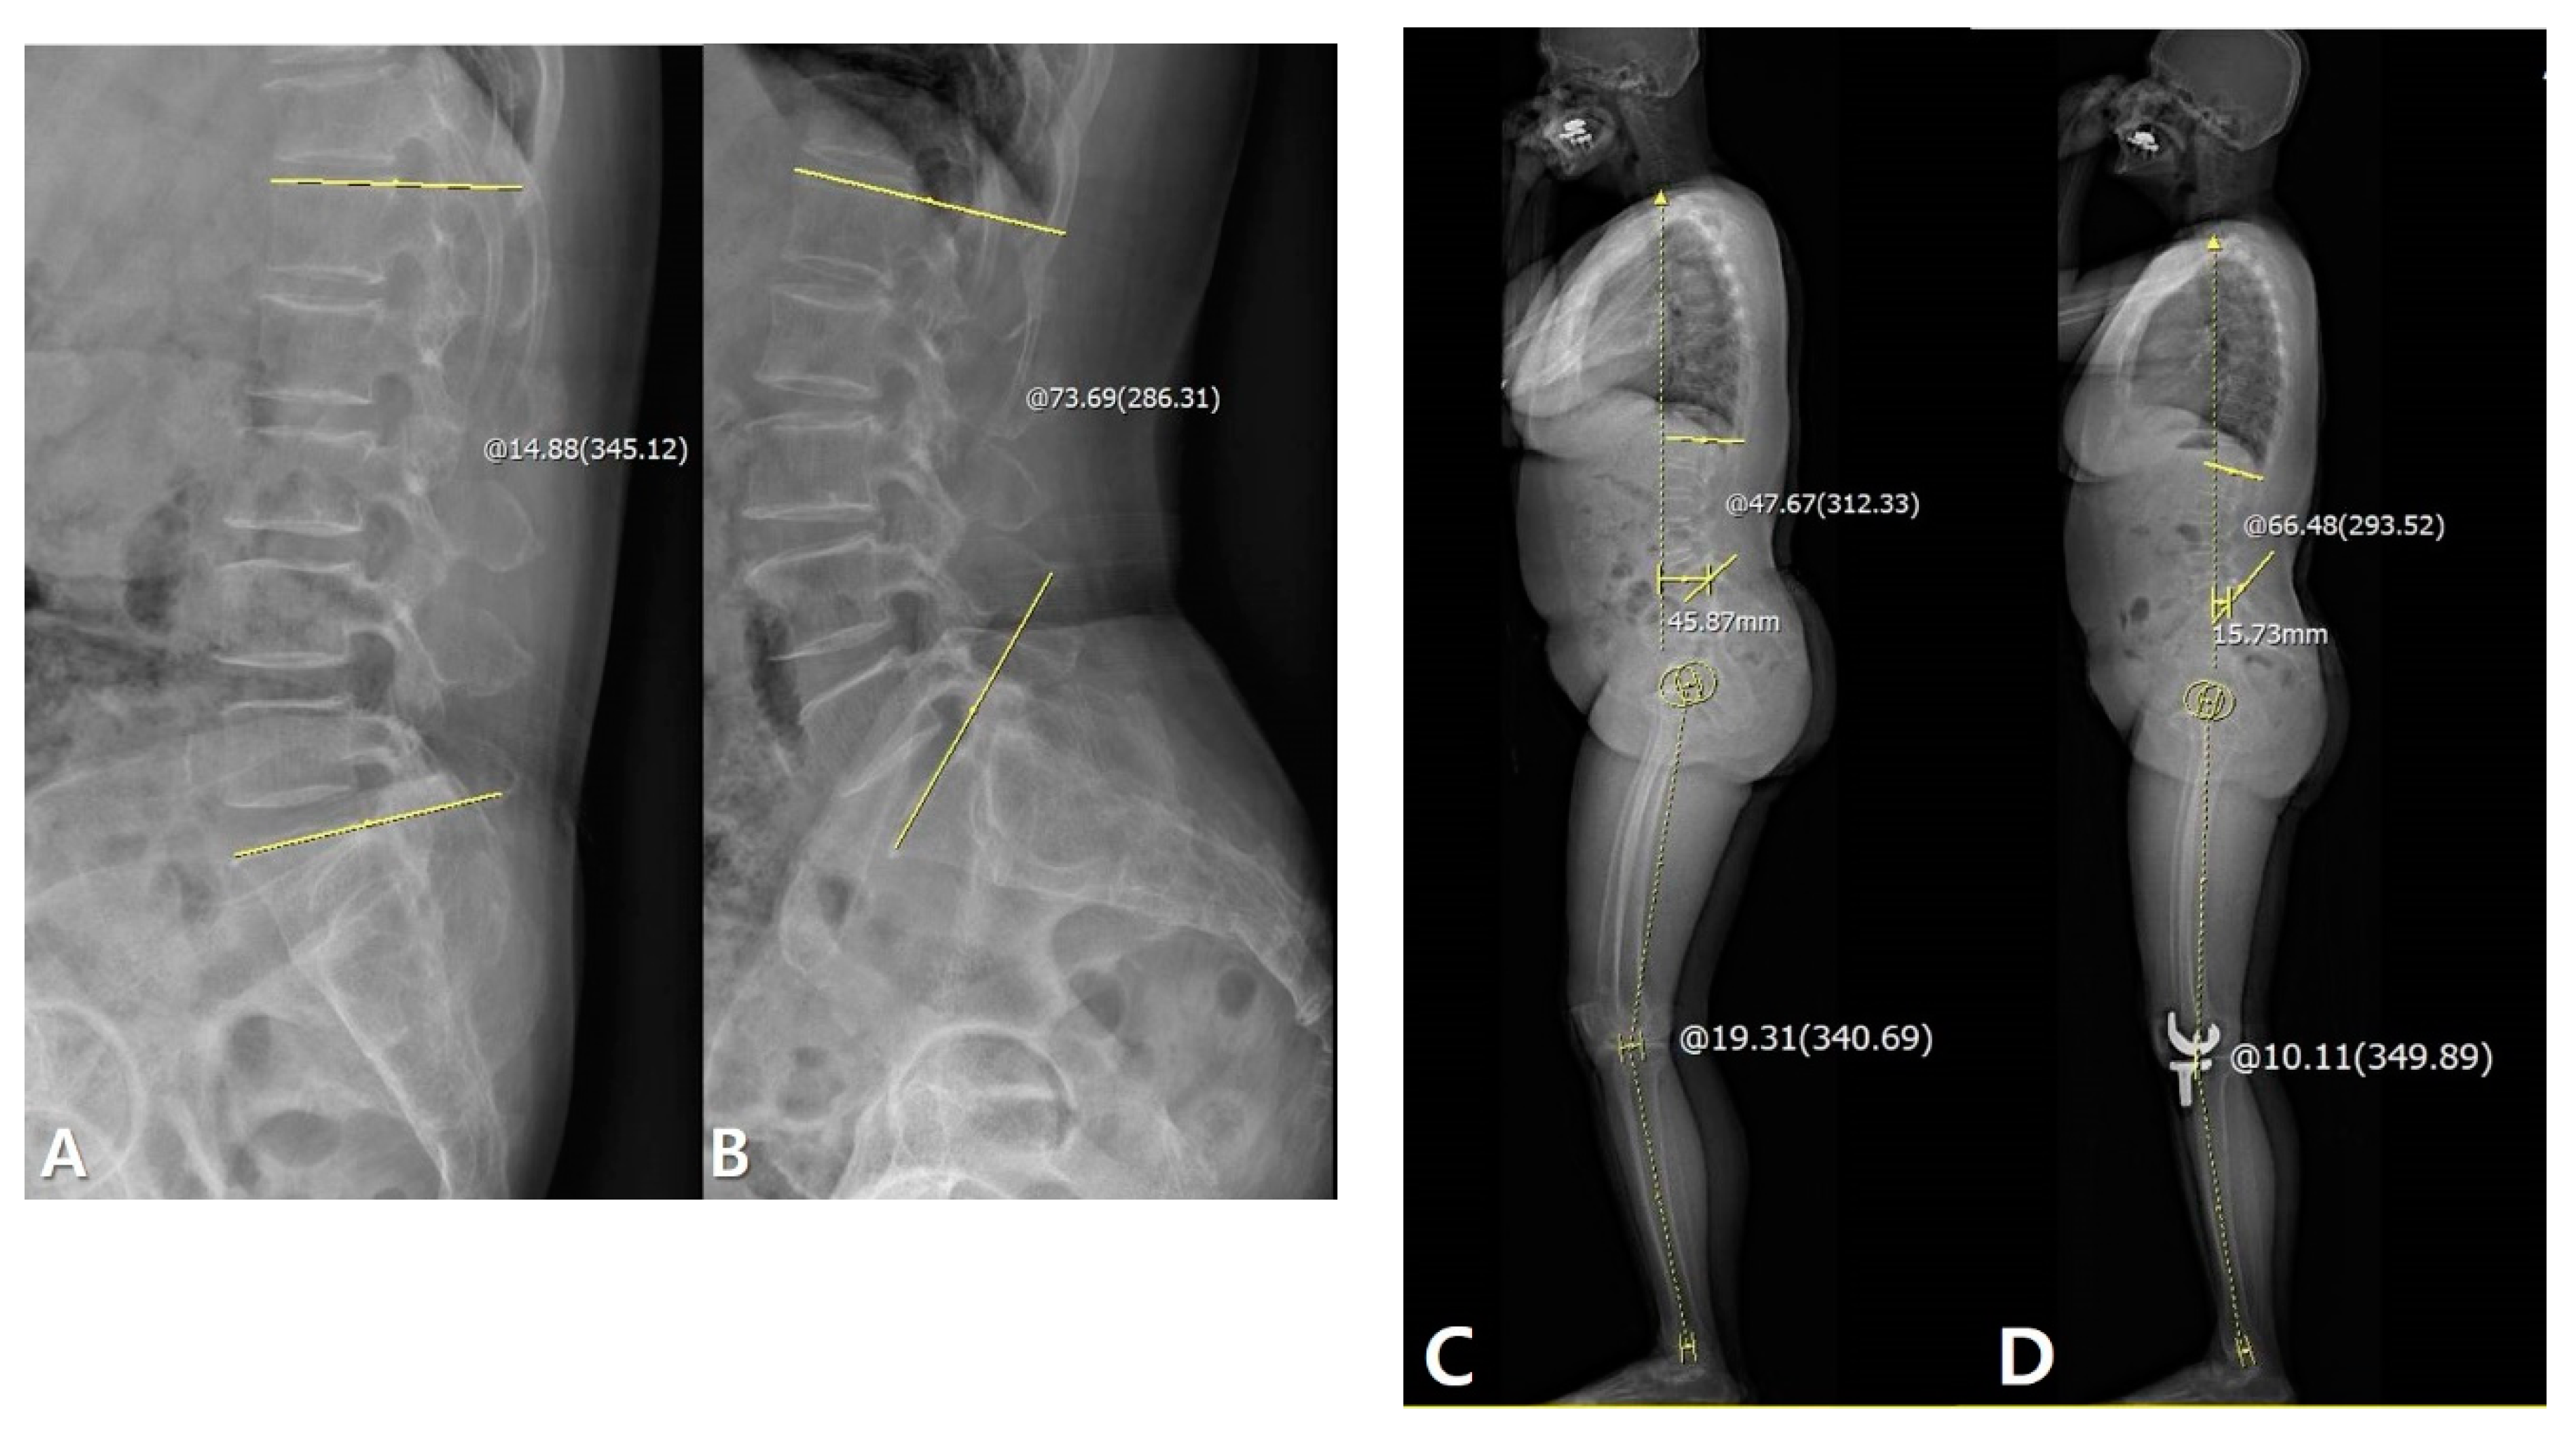

2.2. Changes in Sagittal Alignment after TKA Considering Lumbosacral Flexibility

2.3. Disparity after TKA Considering Lumbosacral Flexibility

3.1. Changes in Sagittal Alignment after TKA Considering Lumbosacral Flexibility

3.2. Disparity after TKA Considering Lumbosacral Flexibility